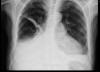

EAP

Edema cisural en EAP